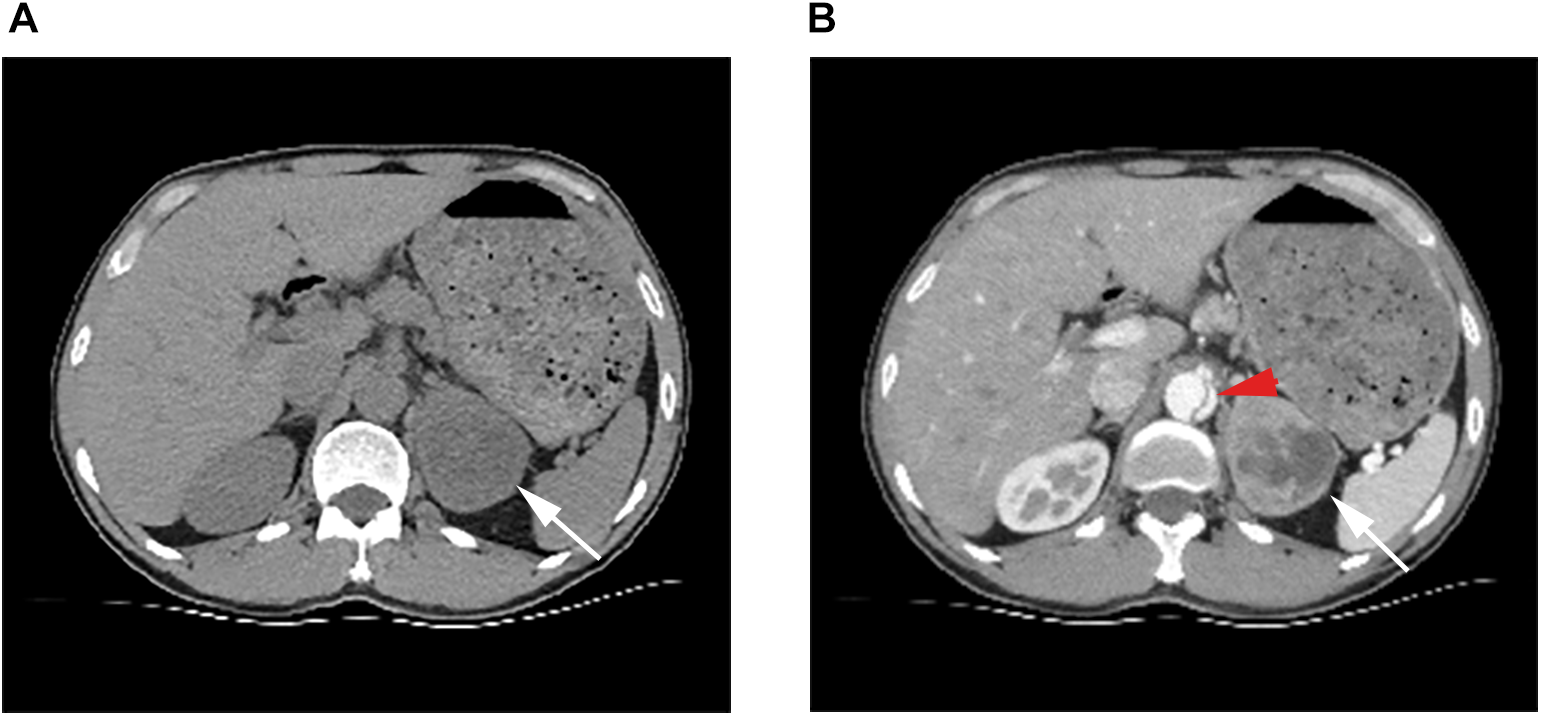

Figure 2

(A) Ct scan showing a soft tissue mass in the left adrenal gland with uneven internal density, clear borders, and regular shape. (B) White arrows point to the left adrenal mass in the arterial phase, which is significantly enhanced and necrotic inside. Red arrows point to dissection of the abdominal aorta.

Physical examination revealed an acutely ill face, clear consciousness, poor spirit, heart rate of 125 beats/min, blood pressure of 210/94 mmHg, distended abdomen, drum sounds on percussion, no tenderness or rebound tenderness, and the presence of femoral and dorsalis pedis pulses. According to the aortic dissection detection risk scoring (ADD-RS) system proposed by the aortic diagnosis and treatment guidelines in 2014, ADD-RS = 1. The etiology of the patient was unknown; clinicians could not rule out aortic dissection, urinary calculi, or other related diseases; therefore, echocardiography and abdominal urinary ultrasonography were performed on the patient. Echocardiography showed normal findings, and abdominal ultrasonography revealed a mass in the left adrenal region (72 × 57 mm, Figure 1). Contrast-enhanced computerized tomography (CT) of the abdomen revealed that the intimal flap moved inward from the descending part of the thoracic aorta to the level of the bilateral common iliac arteries, the lumen showed “double-lumen” changes, the right renal artery opened into the false lumen, and the left renal artery opened into the true lumen, consistent with aortic dissecting aneurysm (Stanford type B). A soft tissue mass was observed in the left adrenal gland, with uneven density, approximately 61 × 53 mm in size, with a clear boundary, and with significant enhancement after contrast-enhanced scanning in which there was necrosis; pheochromocytoma was first considered (Figure 2). The patient subsequently underwent aortic computed tomographic angiography (CTA), which revealed Stanford TBAD (Figure 3). Laboratory tests showed a 24-h urine vanillylmandelic acid (VMA) level of 20.51 mg/24 h (reference value: ≤12 mg/24 h) and a D-dimer level of 6.75 mg/L (reference range 0.0–0.5 mg/L).